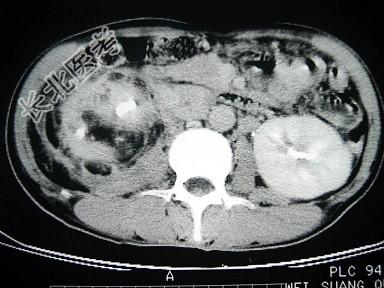

- 单项选择题女,43岁, 右腰部疼痛不适2年余,加重3天, CT及MRI检查如图,应诊断为 ( )

A、右肾癌

B、右肾错构瘤合并出血

C、右肾脂肪瘤

D、右肾脂肪肉瘤

E、右肾海绵状血管瘤